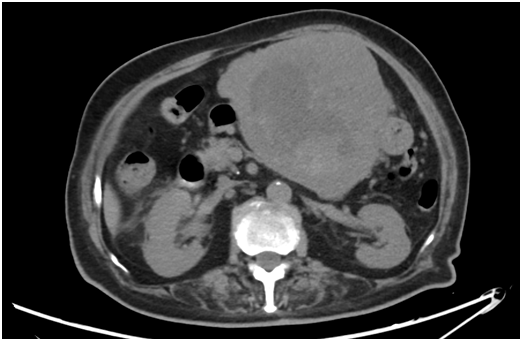

92岁的夏奶奶因“腹痛、腹胀伴食欲减退”至大丰某医院就诊,CT检查提示:上腹腔占位,增强CT提示肝胃间隙巨大占位,MT可能。外院考虑手术风险极大,建议至我院就诊。